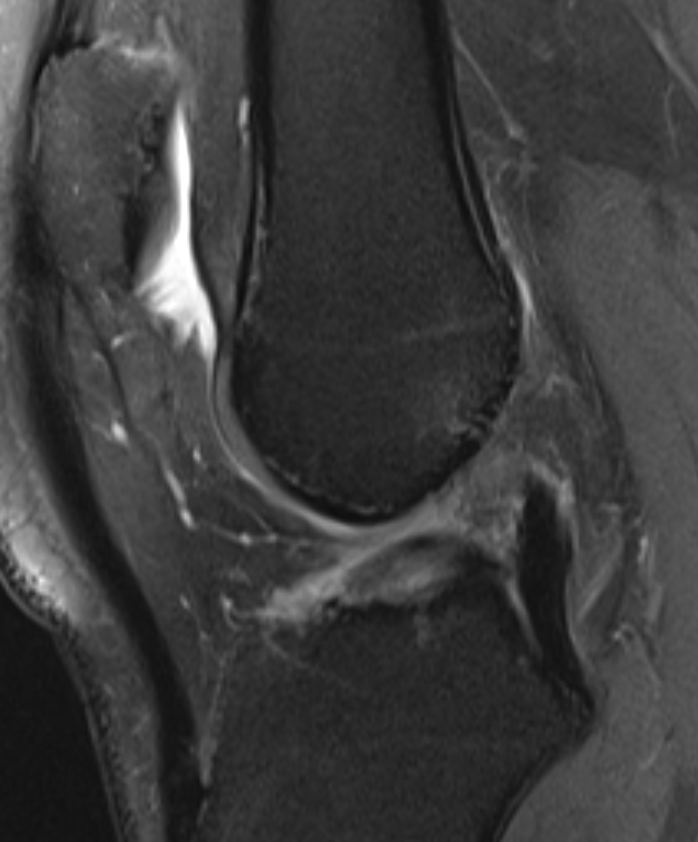

Occipital condyle avulsion fracture is often difficult to see on sagittal images

#radres always look on coronal and axial images, add this to your checklist#radiology#spine@NASSspine#EMRAd#FOAMed#spinetrauma#injurypic.twitter.com/lC7l73mnEj